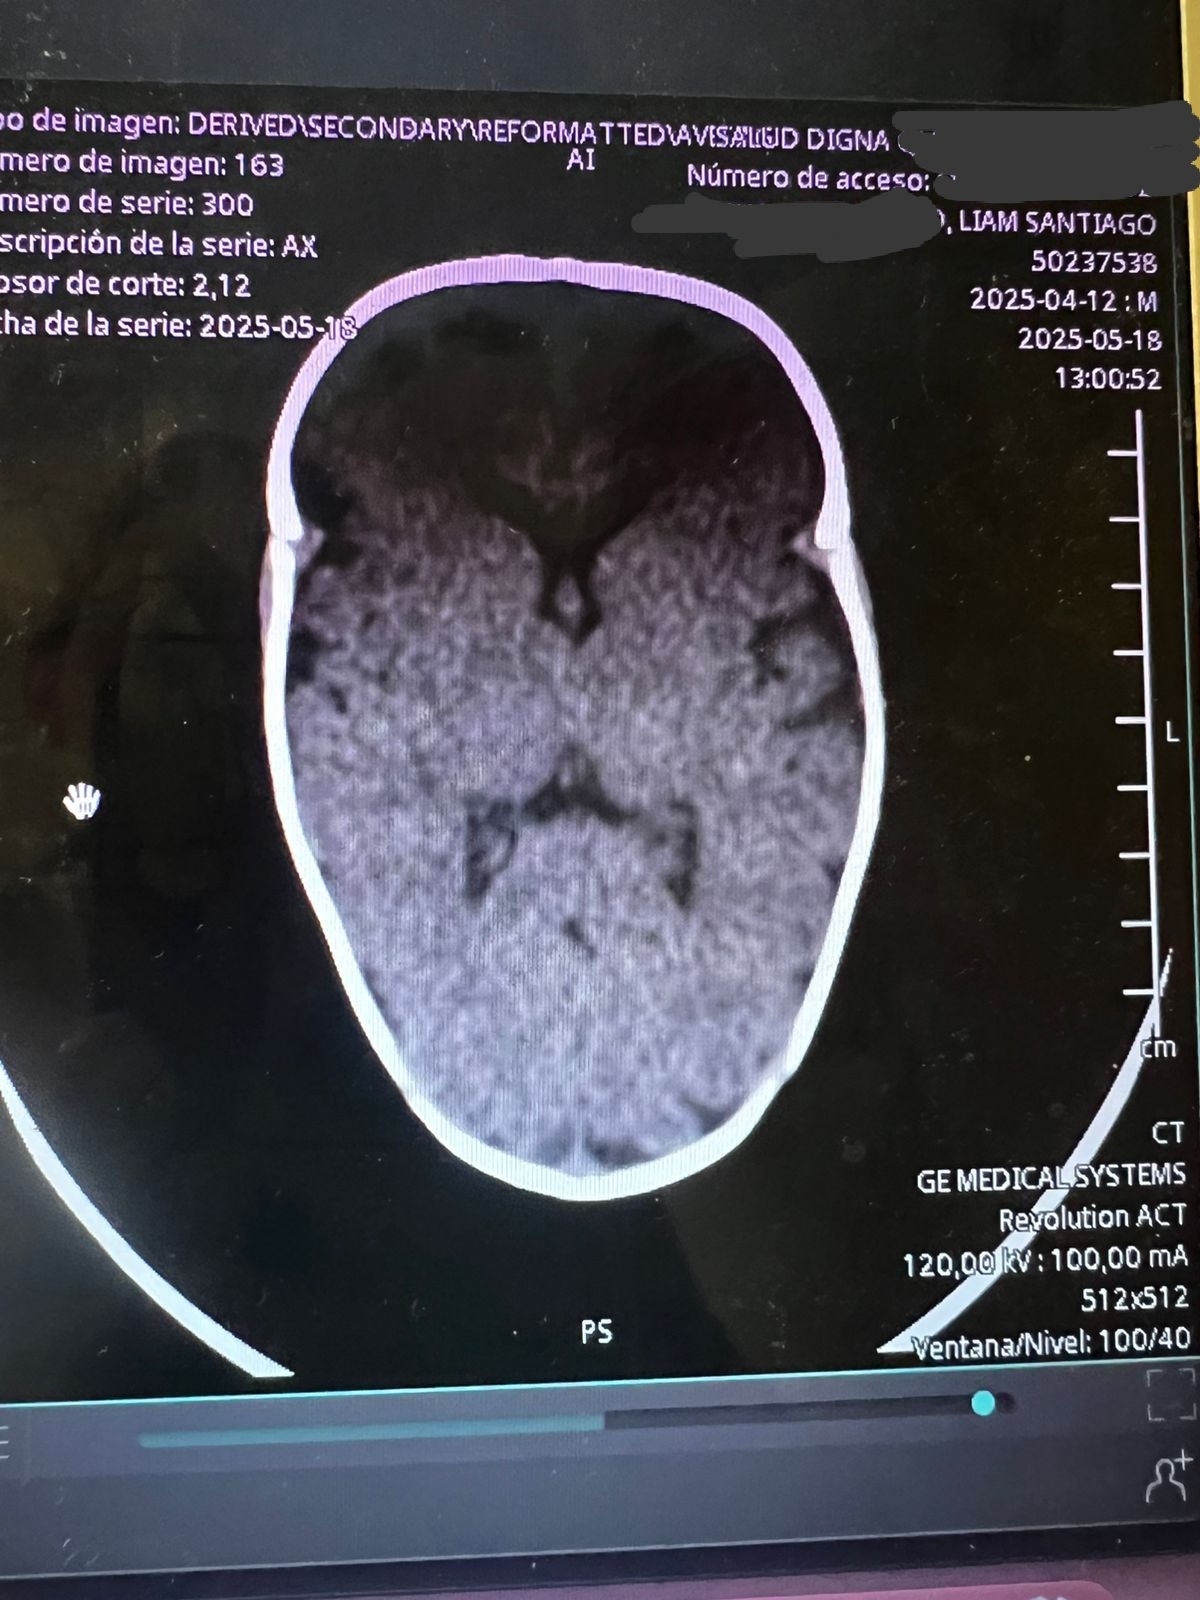

Hola mi nombre es Diana y hace aproximadamente un mes nació mi sobrino Santiago, ayer le acaban de detectar craneosinostosis y es necesario realizarle una cirugía en su cabecita lo más rápido posible para que su cerebro pueda tener un desarrollo adecuado, para realizar esta cirugía en los hospitales públicos hay lista de espera de seis meses aproximadamente y debido a la urgencia y que vamos contra reloj ya que se debe realizar en los primeros meses de vida que es cuando es menos riesgosa la operación por eso la única opción que nos queda es realizarla en un hospital privado por eso el costo tan elevado, les pido de todo corazón su ayuda cualquier aportación es de gran ayuda para poder juntar el dinero cuanto antes y el pequeño Santi pueda ser operado cuanto antes.